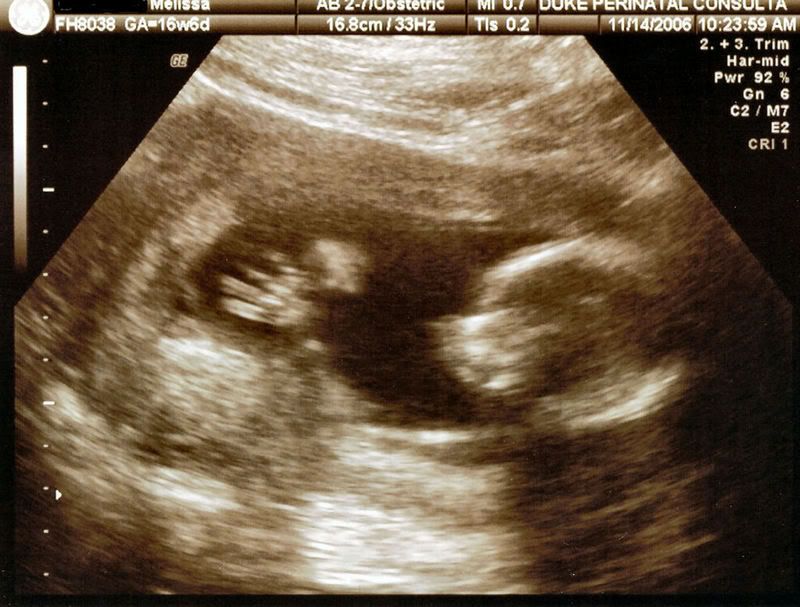

My daughter had her 18 week ultrasound today and we have a little boy. He was quite proud to display his little tallywhacker at the appropriate moment. We are so thrilled and tickled that he seems very happy and healthy. As soon as I get the pictures loaded onto photo bucket I will post the handsome little devils pictures. |

here he is asleep http://i11.photobucket.com/albums/a190/the...b4fan/Sleep.jpg from the side with his little hand open http://i11.photobucket.com/albums/a190/the...an/openhand.jpg Here is his little face http://i11.photobucket.com/albums/a190/the...4fan/Face-1.jpg He had ginormous feet http://i11.photobucket.com/albums/a190/the...ab4fan/Foot.jpg His defining moment http://i11.photobucket.com/albums/a190/the...fab4fan/Boy.jpg |